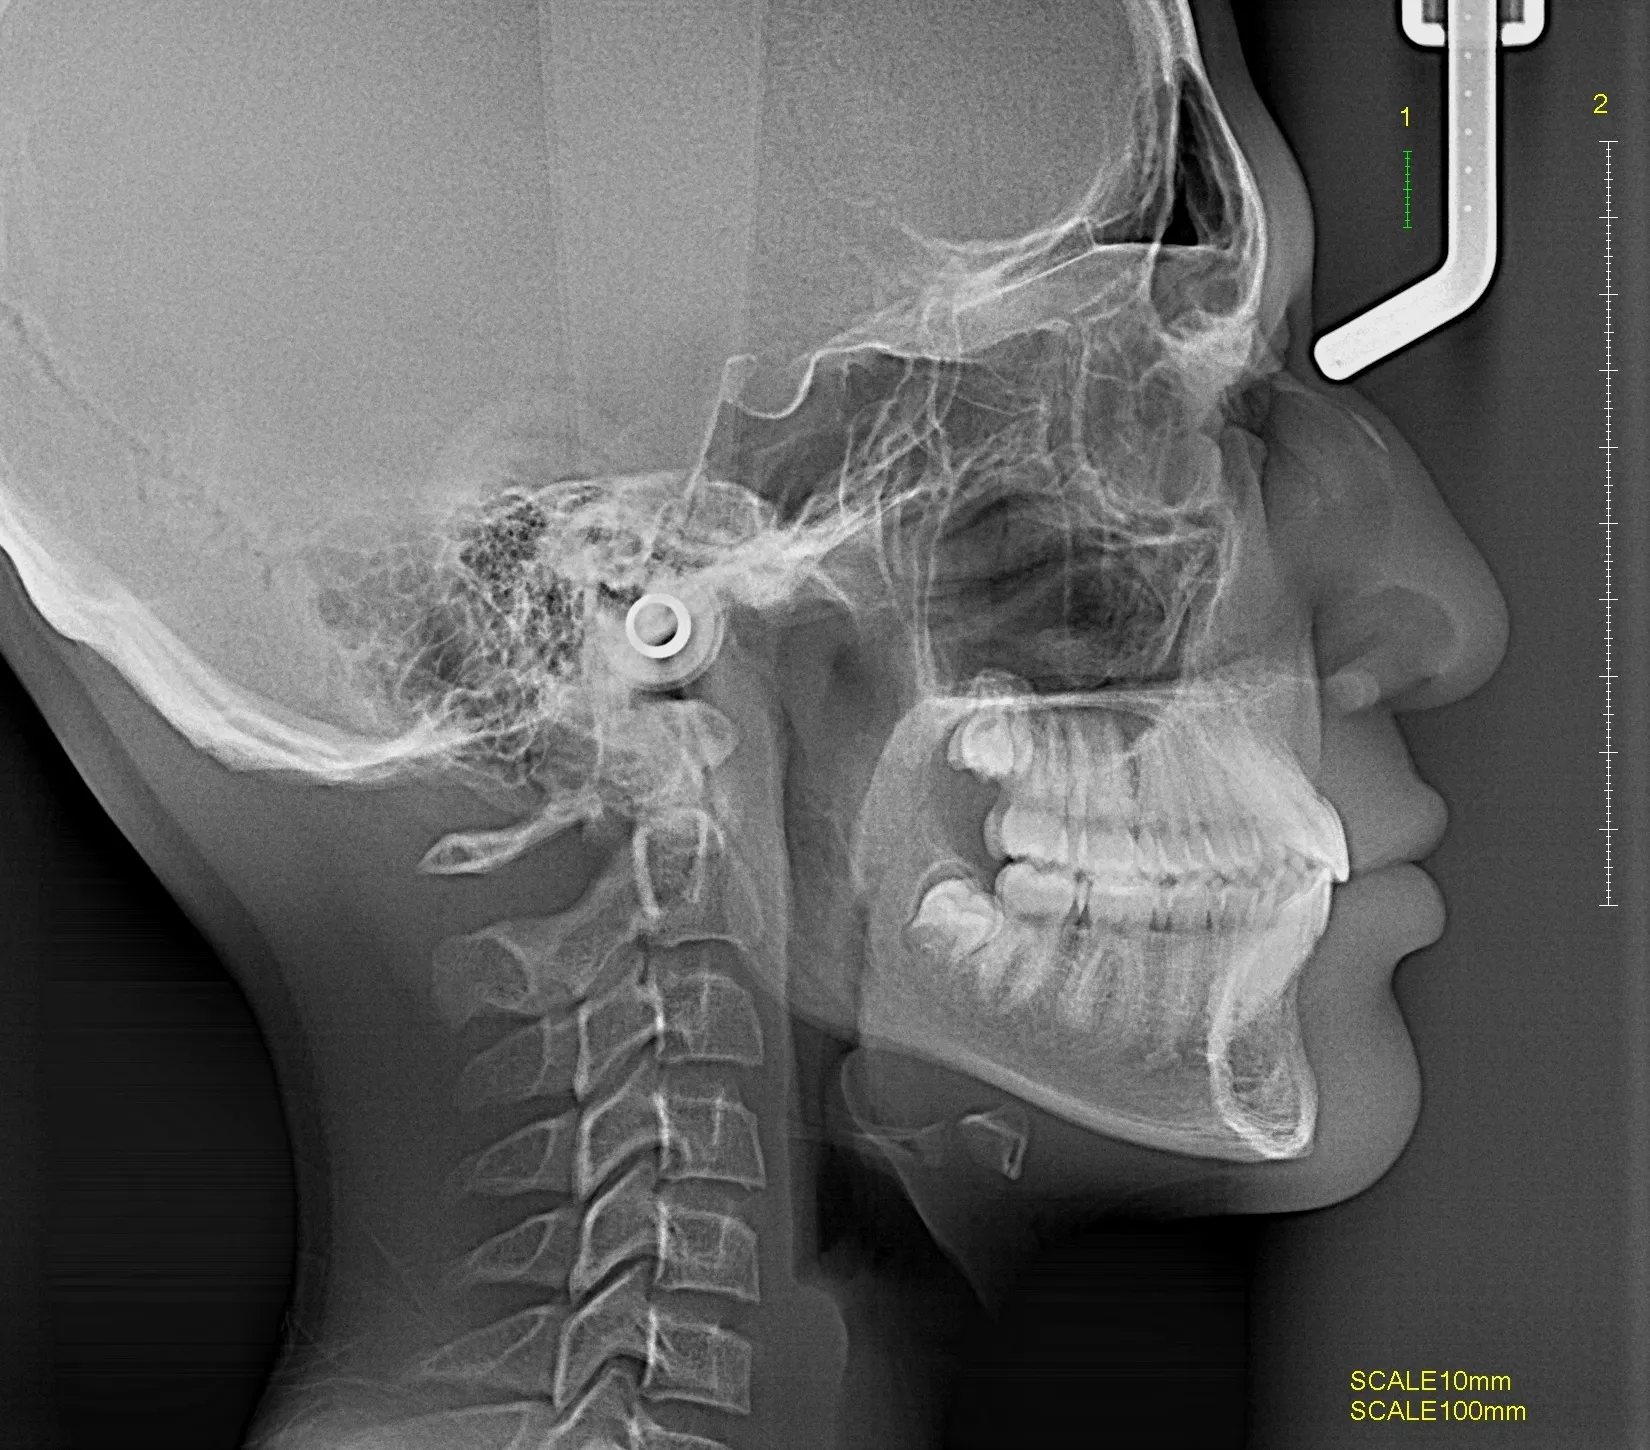

Radiografías Extraorales

Las radiografías extraorales permiten obtener imágenes completas de los maxilares, la articulación temporomandibular (ATM) y las estructuras faciales sin colocar el sensor dentro de la boca.

Realizamos estudios como radiografía panorámica, cefalométrica, de senos paranasales y de ATM, esenciales para tratamientos de ortodoncia, cirugía y diagnóstico integral.